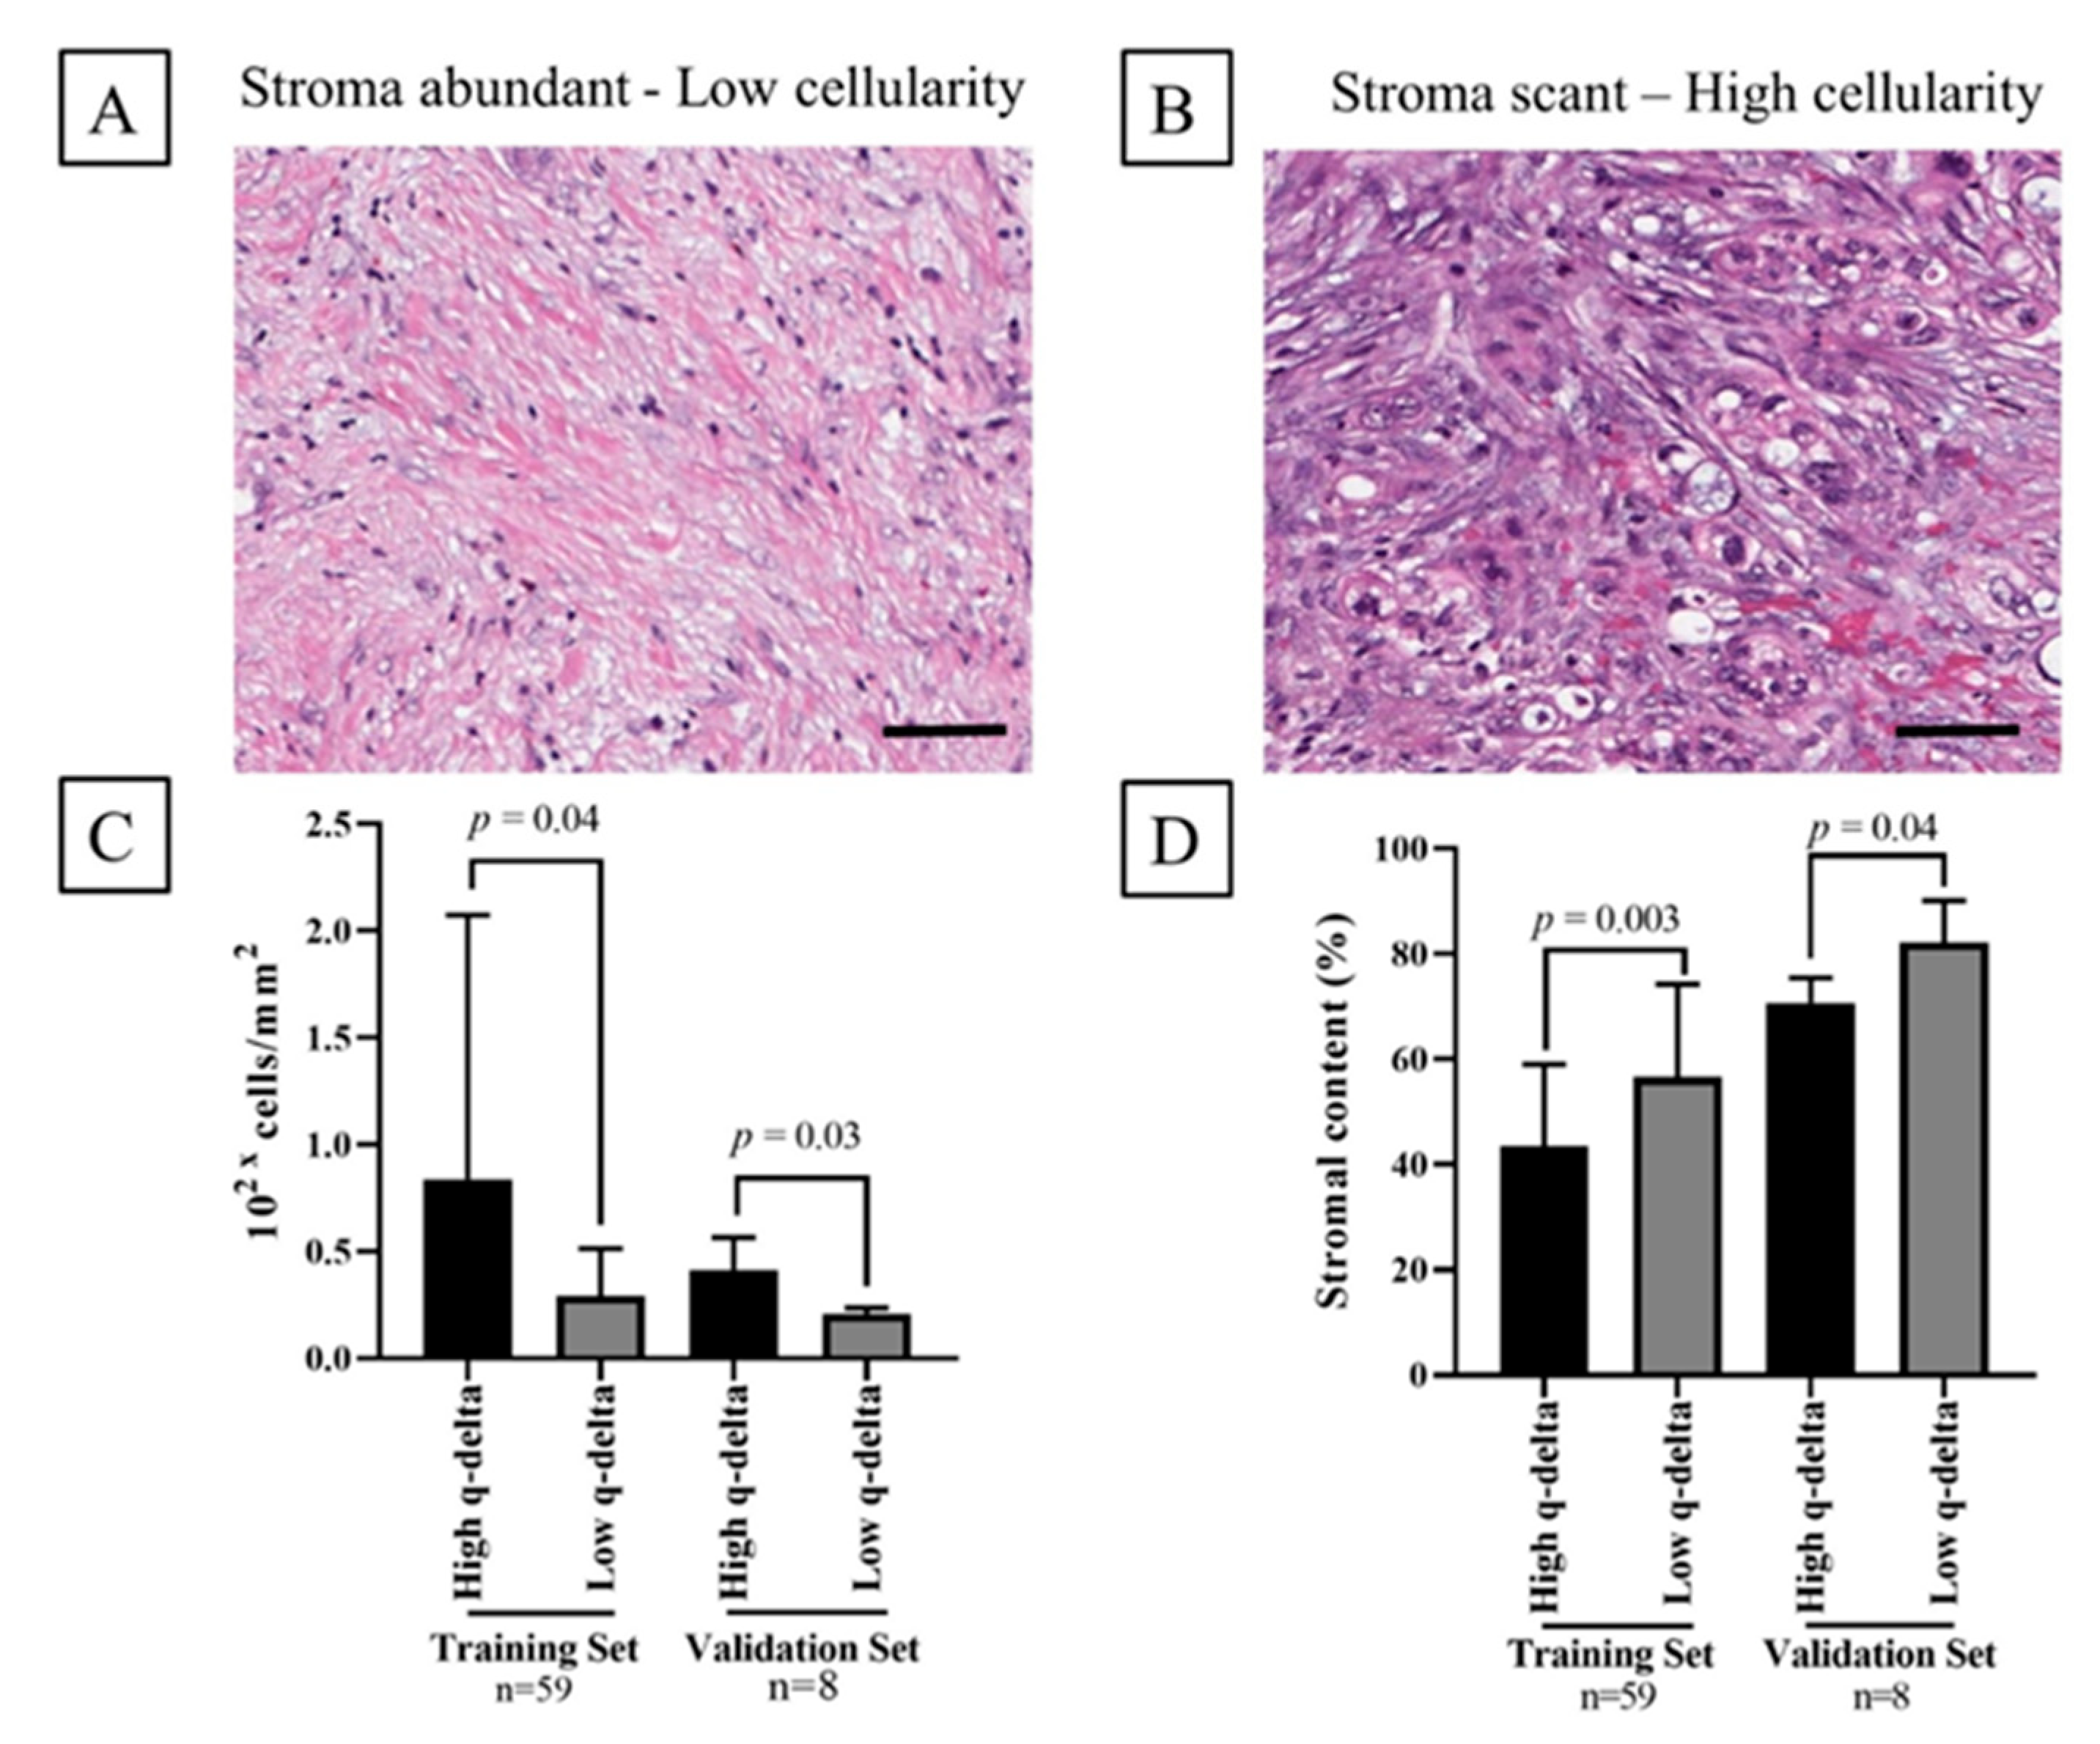

2.5. Association between the q-delta and Tumor Stromal Content

4.7. Histopathological Analysis